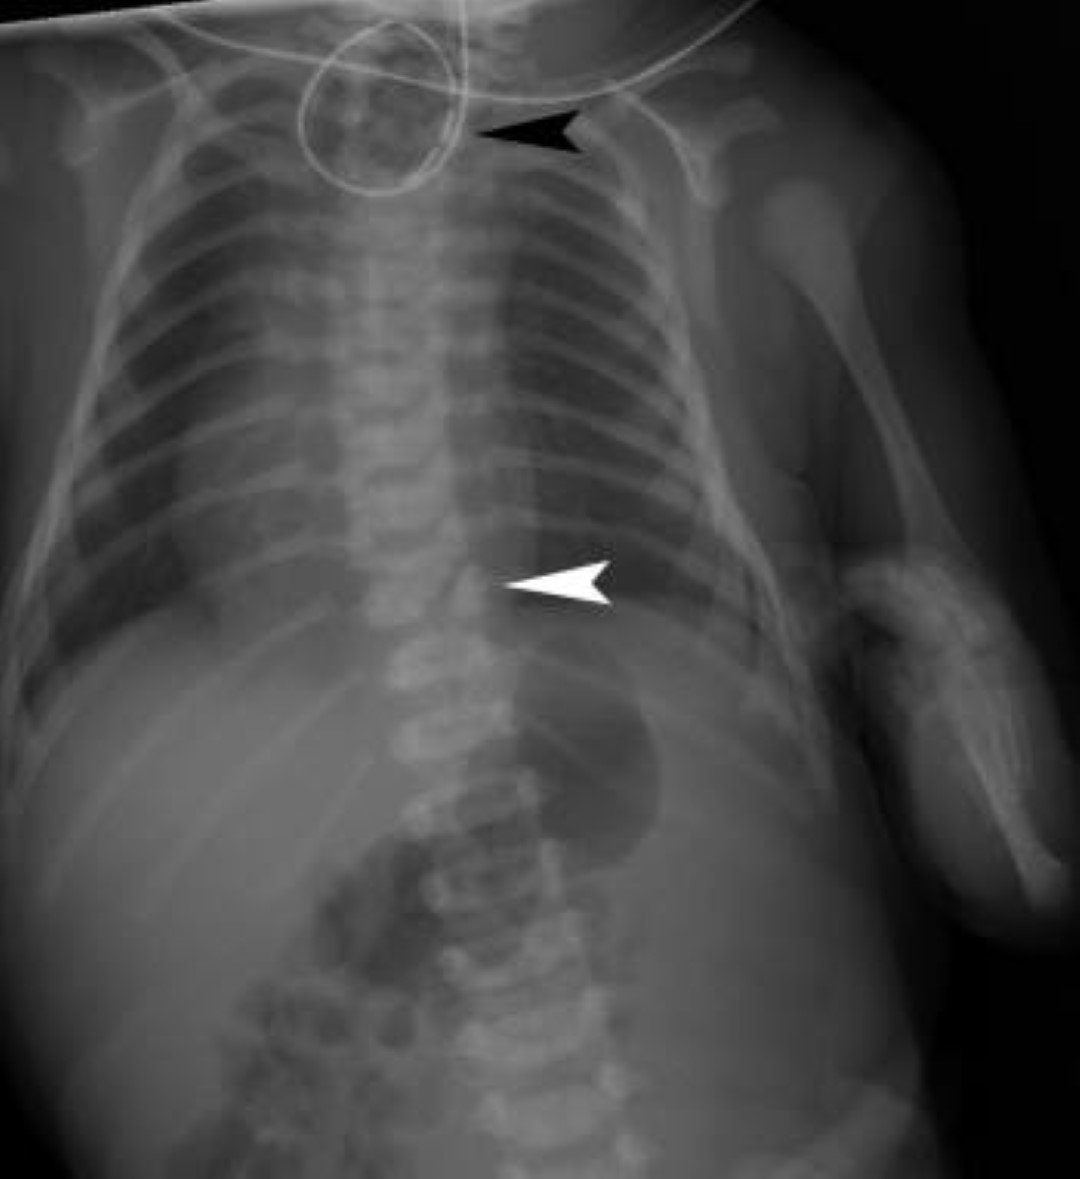

Es un defecto de nacimiento en el que parte del esófago del bebé (el tubo que conecta la boca con el estómago) no se desarrolla adecuadamente. La atresia esofágica es un defecto de nacimiento del esófago (tubo de deglución) que conecta la boca con el estómago. En los bebés que presentan atresia esofágica, el esófago tiene dos secciones separadas (el esófago superior y el esófago inferior) que no se conectan. Al tener este defecto, el bebé no puede pasar alimentos de la boca al estómago y a veces tiene dificultad para respirar. La atresia esofágica con frecuencia se presenta con otro defecto de nacimiento llamado fístula traqueoesofágica, en el que una parte del esófago está conectada con la tráquea.